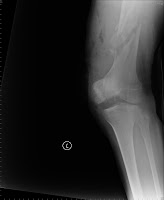

Amazing remodeling of femoral supracondylar comminuted fracture

Severe comminuted fracture of supracondylar fracutre

Post-OP

8 months

Amazing remodeling: 17 months

pain-free and full-weight-bearing